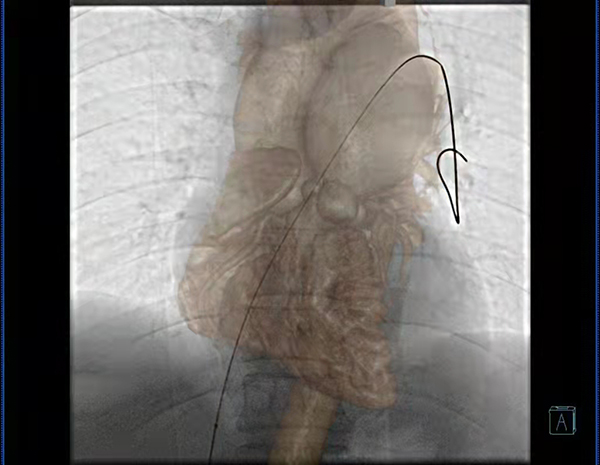

此次在心臟外科進行的肺動脈瓣閉式擴張術中,放射科技師成功運用CTA與3D-DSA影像融合技術,將患者術前肺動脈CTA薄層影像與胸部3D-DSA影像進行融合得到肺動脈的三維路徑,通過旋轉(zhuǎn)融合的三維路徑來為術者提供參考,選擇最佳的造影角度建立手術入路,引導導絲通過建立的手術入路從右心室進入肺動脈,從而達到擴張肺動脈瓣的目的。